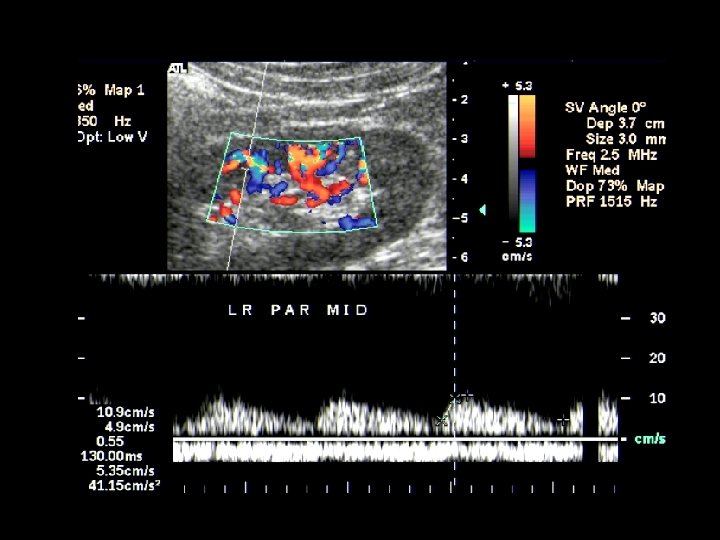

RA US can evaluate the parenchymal flow as well Note increased acceleration time (AT) and borderline resistive index (RI) RI 0. 53 AT 140 m/s